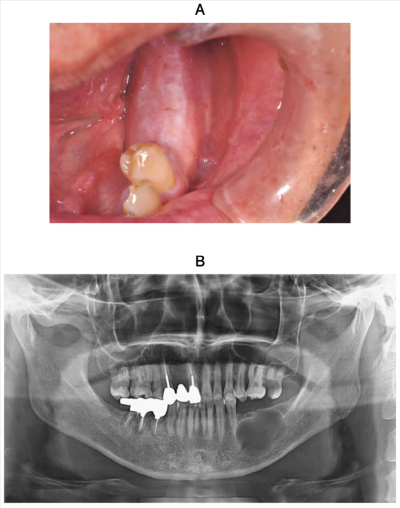

55歳の男性。下顎左側臼歯部の腫脹を主訴として来院した。5年前に気付いたがそのままにしていたという。診察の結果、生検と開窓を行うこととした。初診時の口腔内写真、エックス線写真、CT、生検前の穿刺液及び生検時のH-E染色病理組織像を別に示す。